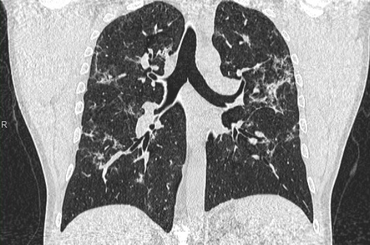

Még fél év után is kimutathatók CT-vel a koronavírus okozta tüdőelváltozások

A hazai képalkotó diagnosztikai piac vezetője, az Affidea Magyarország még biztonságosabbá tette COVID-protokollját minden egészségügyi...